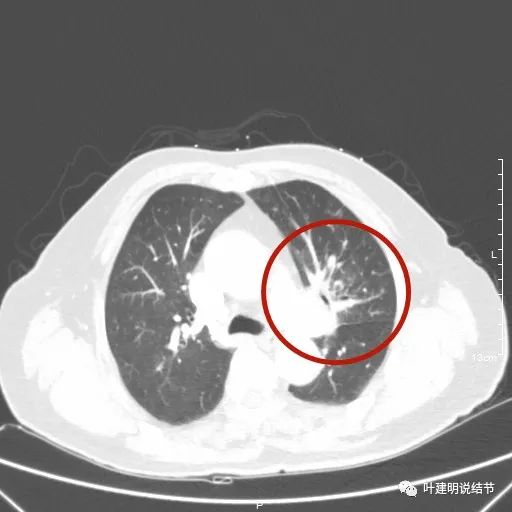

肺窗见原左上叶巨大占位已经明显缩小,甚至几乎不见了!而且上图示左上叶支气管清晰可见,内壁变光滑。纵隔窗增强又是如何的呢?

可见效果相当的好,如果我们把差不多同样层面的放到一起对比,更能显示化疗加免疫的惊人效果:

我样的治疗效果,显然超出了我们之前的预期,那么接下来拟选择行手术治疗,初定左上叶袖式肺叶切除加淋巴结清扫,但因为肺门区仍有软组织影,与肺动脉的关系仍密切,肿瘤与肺动脉间能否游离开来还是未知数,但至少得努力争取,鉴于患者年纪虽大,肺功能指标尚可,血气分析也基本正常,所以与患方沟通后确定行手术探查,但也也说明有万一全肺切除的可能(虽然这种可能性较小)。